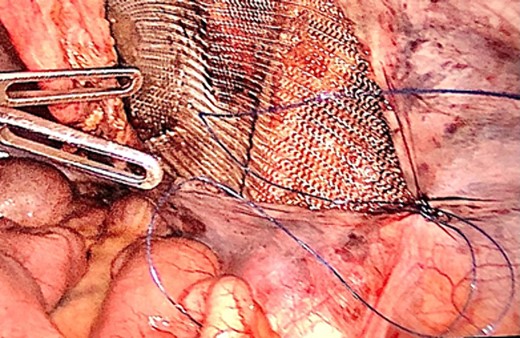

We also identified the intra-abdominal testis, along with the spermatic cord and testicular vessels (Fig. 2). The right side was normal. Orchidectomy was performed using LigaSure. Testes were extracted through the umbilical port site. After the orchidectomy was performed, left hernioplasty using a lightweight mesh was performed via the TAPP procedure (Fig. 3). The operative time was 75 min. The postoperative course was uneventful, and the patient was discharged on postoperative day. The specimen revealed an atrophic testis without malignancy. Postoperatively, semen analysis revealed improvement, and after 2 years, the patient was married and had two children. To date, there has been no recurrence of the hernia.

Laparoscopic view of the intraabdominal testicle and the inguinal hernia associated.

The hernia sac was found to invaginate the right inguinal ring, and after drawing back the hernia sac, the atrophic testis, along with the spermatic cord and testicular vessels, was revealed (Fig. 4). Heavyweight mesh was used (Fig. 5). The operative time was 95 min. No complications were noted and the patient was discharged on postoperative day 2. Pathological examination revealed no malignancy or spermatogenic abilities. No improvement in the semen analysis results was noted during the follow-up period. To date, there has been no recurrence of the hernia.

Laparoscopic view of the peritoneal suture in the TAPP procedure performed after orchiectomy.